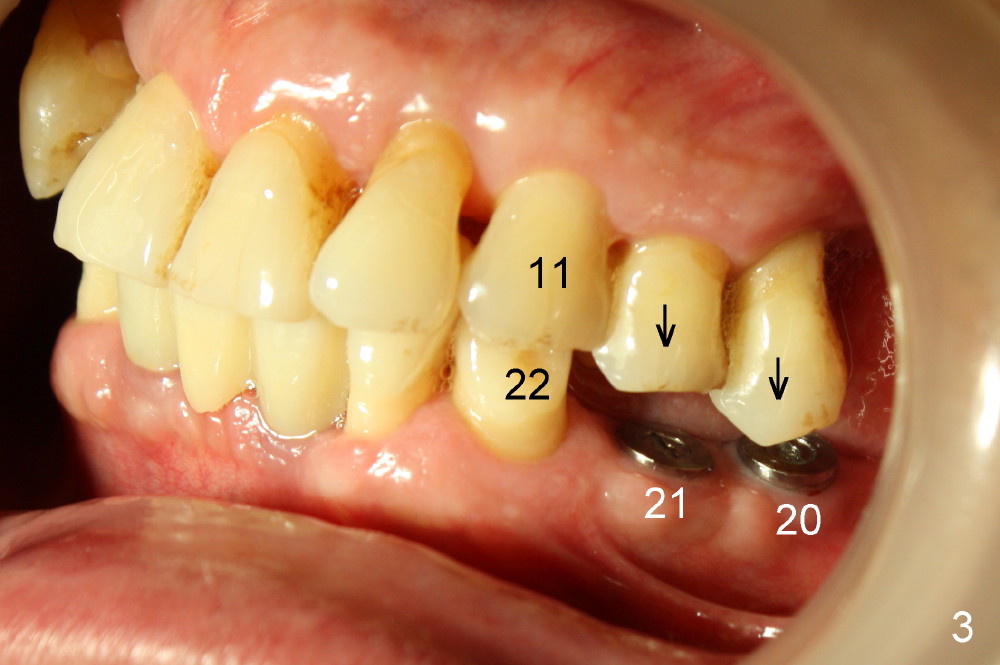

Clinical exam reveals that the upper midline appears to be deviated to the right (Fig.2), while the left canine relationship is Class II (Fig.3). Therefore, the upper anterior teeth (#9-12) will be moved distally orthodontically. When the tooth #13 is extracted, the immediate implant should be placed more distal than usual. This implant, once osteointegrated, will be used an anchorage for distaliztion of the teeth mesial to it.